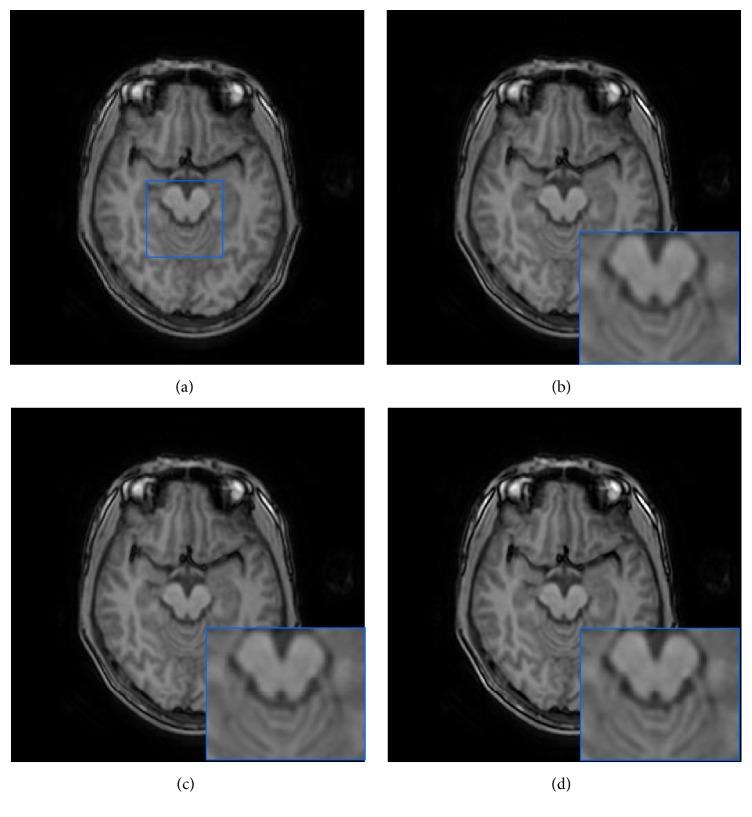

The spatial resolution of magnetic resonance imaging (MRI) is often limited due to several reasons, including a short data acquisition time. Several advanced interpolation-based image upsampling algorithms have been developed to increase the resolution of MR images. These methods estimate the voxel intensity in a high-resolution (HR) image by a weighted combination of voxels in the original low-resolution (LR) MR image. As these methods fall into the zero-order point estimation framework, they only include a local constant approximation of the image voxel and hence cannot fully represent the underlying image structure(s). To this end, we extend the existing zero-order point estimation to higher orders of regression, allowing us to approximate a mapping function between local LR-HR image patches by a polynomial function. Extensive experiments on open-access MR image datasets and actual clinical MR images demonstrate that our algorithm can maintain sharp edges and preserve fine details, while the current state-of-the-art algorithms remain prone to some visual artifacts such as blurring and staircasing artifacts.

由于多种原因,包括数据采集时间短,磁共振成像(MRI)的空间分辨率常常受到限制。已经开发了几种基于先进插值的图像超分辨率算法来提高MR图像的分辨率。这些方法通过原始低分辨率(LR)MR图像中体素的加权组合来估计高分辨率(HR)图像中的体素强度。由于这些方法属于零阶点估计框架,它们仅包括图像体素的局部常数近似,因此不能完全表示潜在的图像结构。为此,我们将现有的零阶点估计扩展到更高阶的回归,使我们能够通过多项式函数近似局部LR-HR图像块之间的映射函数。在开放获取的MR图像数据集和实际临床MR图像上进行的大量实验表明,我们的算法可以保持清晰的边缘并保留精细的细节,而当前的最先进算法仍然容易出现一些视觉伪影,如模糊和阶梯状伪影。